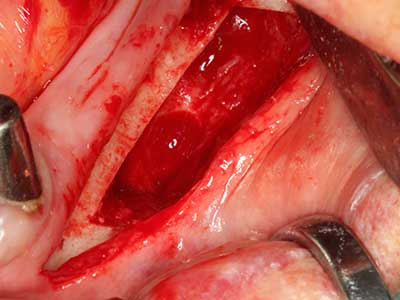

Si es preciso realizar intervenciones quirúrgicas en las que el hueso está en contacto directo con estructuras sensibles, como son los vasos sanguíneos o los nervios, los instrumentos rotativos presentan un enorme potencial de provocar lesiones iatrogénicas. Así, precisamente en la representación de nervios después de una lesión iatrogénica, o en el transcurso de la lateralización de un nervio para resecciones, reconstrucciones o incorporación de implantes, los equipos piezoeléctricos pueden resultar muy útiles para preparar la tapa ósea y retirar las partes de tejido duro cercanas al nervio (fig. 17-20). Por lo general, un ligero contacto del cordón nervioso con el inserto piezoeléctrico no tiene consecuencia alguna; ahora bien, un procedimiento poco cuidadoso con movimientos tipo sierra o piezas de trabajo sobre la base ósea aún existente puede provocar lesiones nerviosas temporales o incluso permanentes. Con todo, el riesgo de sufrir una lesión de este tipo se considera significativamente inferior que en los casos en los que se utilizan sierras y fresas (Pereira, Gealh et al. 2014).